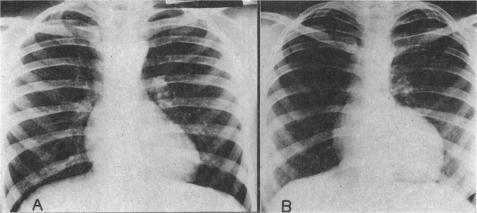

UNILATERAL NOTCHING OF THE RIBS IN CYANOTIC HEART DISEASE.

Br Heart J. 1964 Sep;26(5):620-4. doi: 10.1136/hrt.26.5.620.